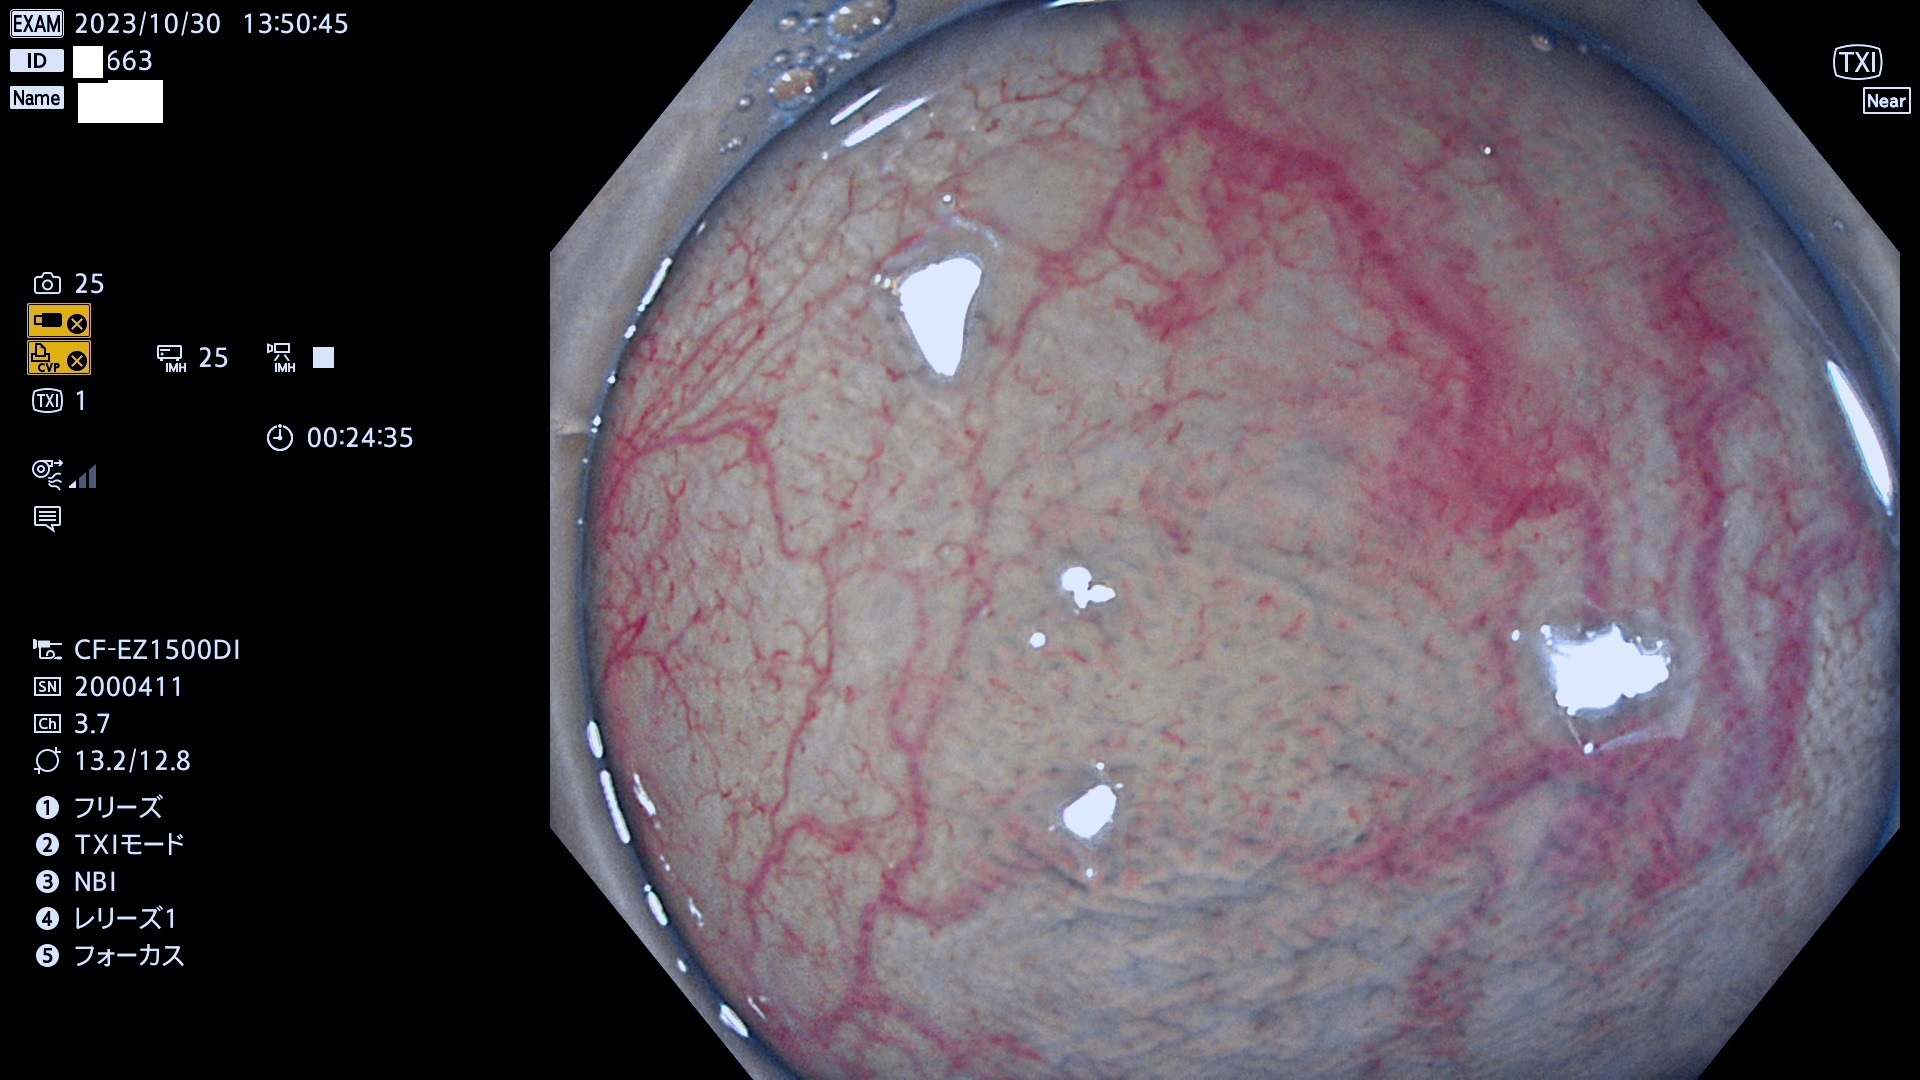

表面型腺腫(Flat Adenoma)の中で、完全に平坦な物をUb、陥凹している物をUcと呼びます。平坦隆起型(Ua)よりも、発見が難しく危険な病変です。このタイプは「内視鏡後・大腸癌の重要犯人」であり、この発見率は「腺腫発見率」よりも、重要な意味があります。

毎週の検査(木・金・土・日)に発見されたUb、Uc型・腺腫を、その週の日曜の夜にUPし1週間、提示します。

抽出の対象期間 2023年10月26日(木)〜10月30(月)の5日間(60件の検査)7件